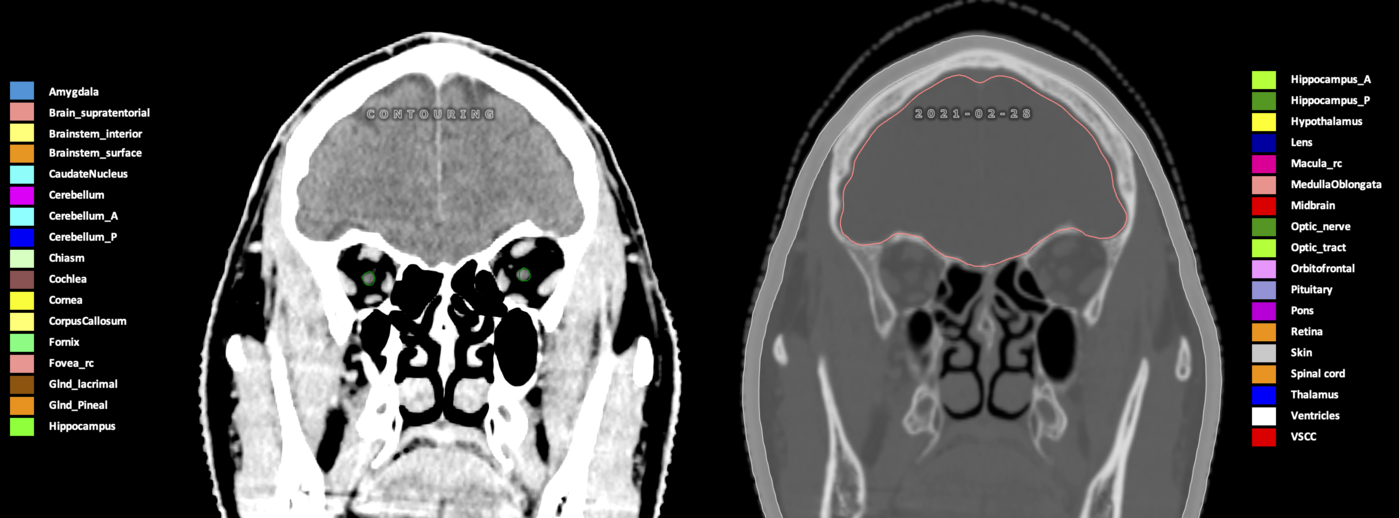

Eekers et al. have published an international neurological atlas for contouring of organs at risk in consensus with the European Particle Therapy Network (EPTN) in 2018 and an update in 2021. The purpose of this consensus atlas is to decrease inter- and intra-observer variability in delineating OARs relevant for neuro-oncology.

Included are all OARs known to be relevant for radiation-induced toxicity in neuro-oncology: brain, brainstem (midbrain, pons, medulla oblongata), chiasm, cerebellum (anterior & posterior), cochlea, cornea, hippocampus (anterior & posterior), hypothalamus, lens, lacrimal gland, optic nerve, pituitary, skin, and vestibular & semicircular canals. To further facilitate research on cognition, vision and radiological changes after irradiation of the brain, potential clinically-relevant OARs are included: amygdala, caudate nucleus, cerebellum (anterior & posterior), corpus callosum, fornix, macula, optic tract, orbitofrontal cortex, periventricular space (PVS), pineal gland, and thalamus.

Three-dimensional delineation of the 25 consensus OARs for neuro-oncology are shown on CT (WW/WL 120/40, 3000/600), 3T MR images, (T1Gd, T2FLAIR 1mm) and 7T MR (MP2RAGE 0.7 mm). All are presented in transversal, sagittal and coronal view.